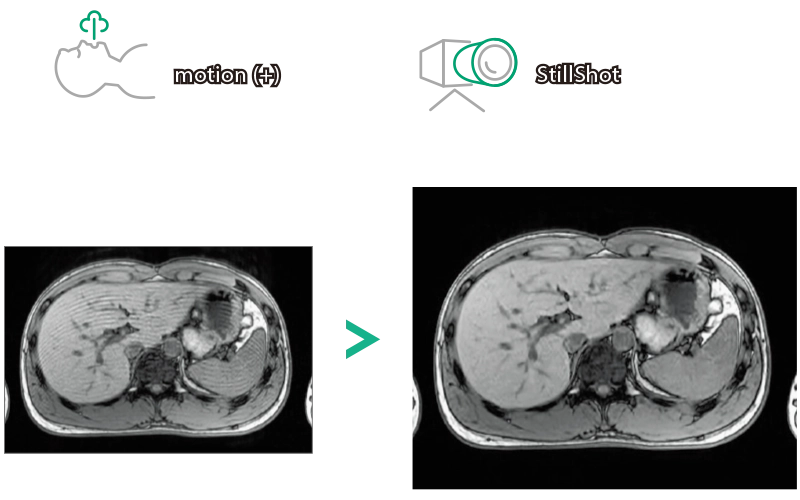

StillShot:The camera detects motion and suppresses the effects of body movement

FLAIR

T1WI Dual Echo (Out) Breath hold